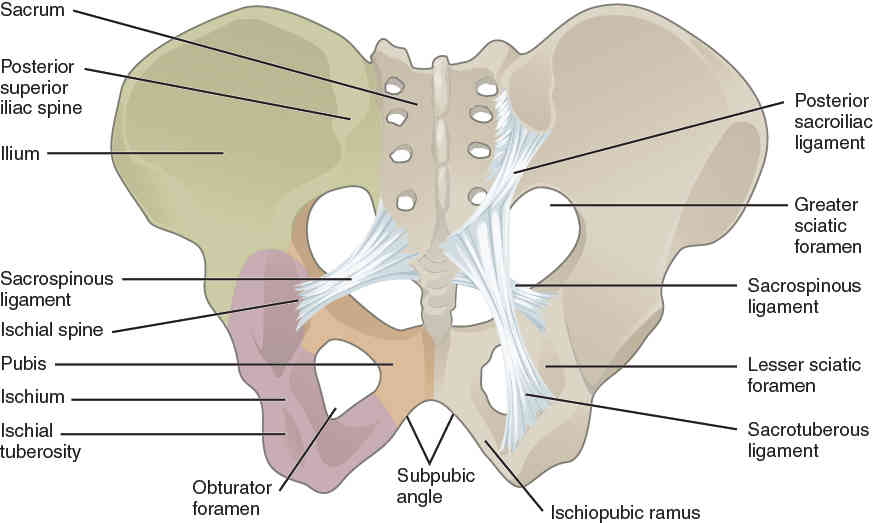

This page is under construction. For now, it is just a resource of the images found in the OpenStax Anatomy and Physiology Handbook. It wil slowly change into a revision tool. Each slide has a number. Use this to refer to the slide. When completed, it will have an unlabelled section, with labelled slides in parallel. On the unlabelled slides, write your answer and use the labelled slide to assess yourself. Keep track by also noting the number on each slide. Improvement at each attempt is important, more so than full marks on a first attempt.